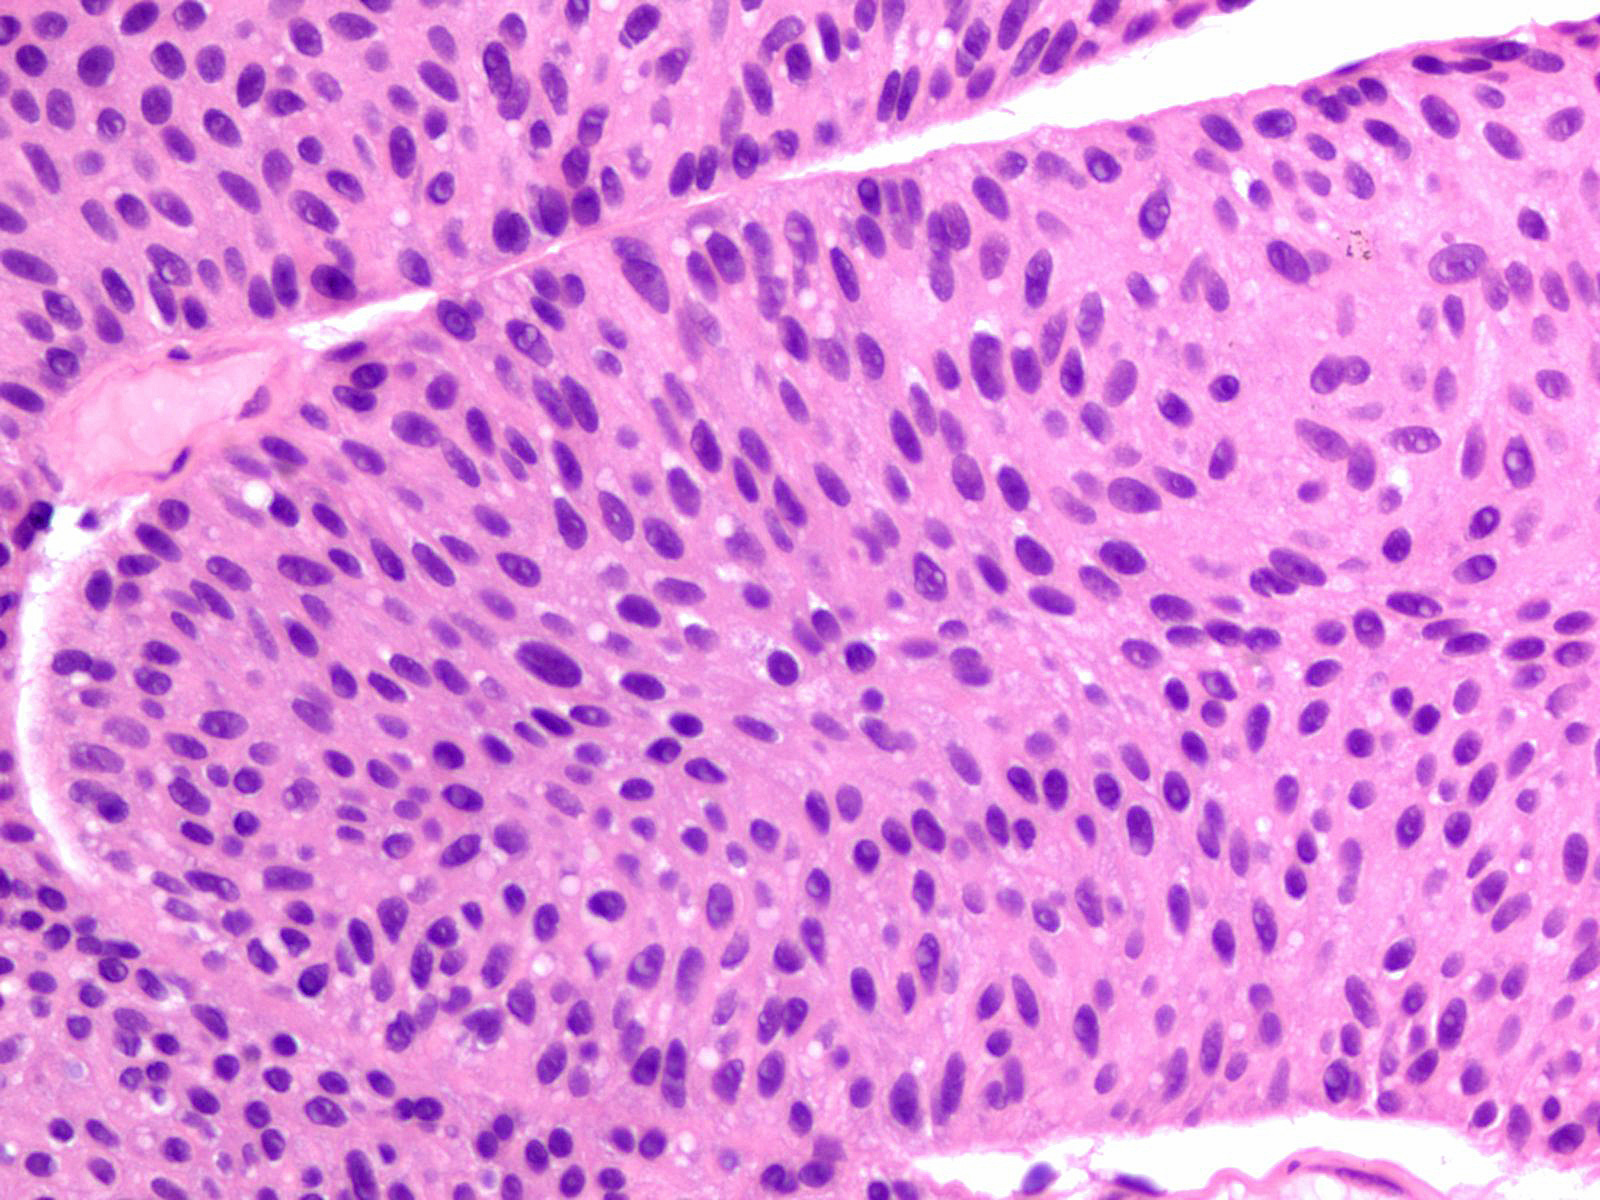

Consensus grade: Low-grade papillary urothelial carcinoma (LG-PUC)

Lesion shows moderate variation in nuclear size, shape and chromatin. Scattered nuclei are significantly enlarged and hyperchromatic relative to other nuclei. Lesion still maintains an overall orderly appearance.